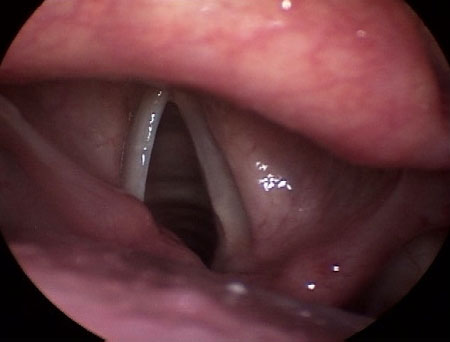

Nódulos, cistos, pólipos, massas fibrosas, granulomas e cicatrizes nas pregas vocais[Figure caption and citation for the preceding image starts]: Pólipo nas pregas vocaisDo acervo da University of Wisconsin School of Medicine and Public Health [Citation ends].

Desenvolvidos em decorrência de uma cicatrização fisiológica anormal de lesão e inflamação imposta no tecido das pregas vocais por estresse mecânico excessivo secundário ao fonotrauma e ao uso vocal excessivo ou indevido.[9][10] Se o fator precipitador for eliminado em um estágio precoce, o edema e os nódulos nas pregas vocais podem ser potencialmente reversíveis.

O fonotrauma é causado por comportamentos vocais como: aumento na tensão ou distensão laríngeas; ataque glótico intenso; nível de frequência inadequado e falta de variabilidade na frequência; fala excessiva; uso prolongado de volume vocal excessivo; uso esforçado e excessivo da voz durante períodos de edema; inflamação ou outras patologias teciduais; tosse e pigarros excessivos; gritos ou outros ruídos; uso indevido da voz ao torcer e gritar em um evento esportivo, dar aulas, atuar como líder de torcida e cantar sem treinamento.[9]

Desidratação, infecções respiratórias crônicas ou recorrentes (bacterianas, virais, fúngicas), TB, refluxo laringofaríngeo, fonotrauma e exposição a irritantes ambientais ou agentes nocivos são fatores contribuintes adicionais no desenvolvimento destas lesões.[9]